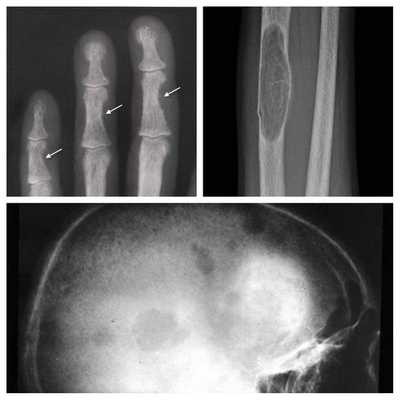

Для оценки тяжести поражения костной системы проводится рентгенография костей стоп, кистей, голени, черепа, денситометрия. Типично выявление признаков диффузной деминерализации костной ткани или фиброзно-кистозного остита. При обзорной урографии, УЗИ почек и мочевого пузыря обнаруживаются одиночные или множественные камни. Состояние органов пищеварения оценивается с помощью УЗИ брюшной полости (желчного пузыря, поджелудочной железы), ЭГДС. При сердечно-сосудистой симптоматике показано выполнение ЭКГ, ЭхоКГ, суточного мониторирования ЭКГ и АД.

Длительное течение заболевания сказывается на формировании костей. Так, н а поздних стадиях вовремя не диагностированного гиперпаратиреоза наблюдаются:

- разрушение дистальных или концевых фаланг конечностей;

- сужение дистального отдела ключиц;

- очаги разрушения костей черепа;

- бурые опухоли длинных костей.